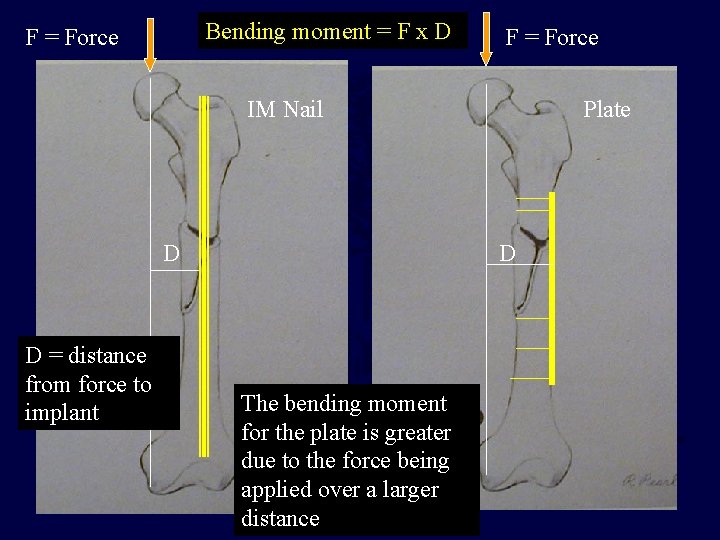

Bending moment = F x D F = Force IM Nail D D = distance from force to implant Plate D The bending moment for the plate is greater due to the force being applied over a larger distance

Femur Fracture Management • Diaphyseal fractures are managed by intramedullary nailing through an antegrade or retrograde insertion site • Proximal or distal 1/3 fractures MAY be managed best with a plate or an intramedullary nail depending on the location and morphology of the fracture